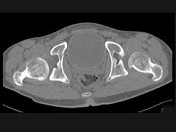

- 单项选择题男,23岁, 跛行,外展受限, 两下肢不等长,结合图像, 最可能的诊断是 ( )

A、髋关节中心脱位

B、髋关节后脱位

C、髋关节前脱位

D、先天性髋内翻

E、髋关节结核